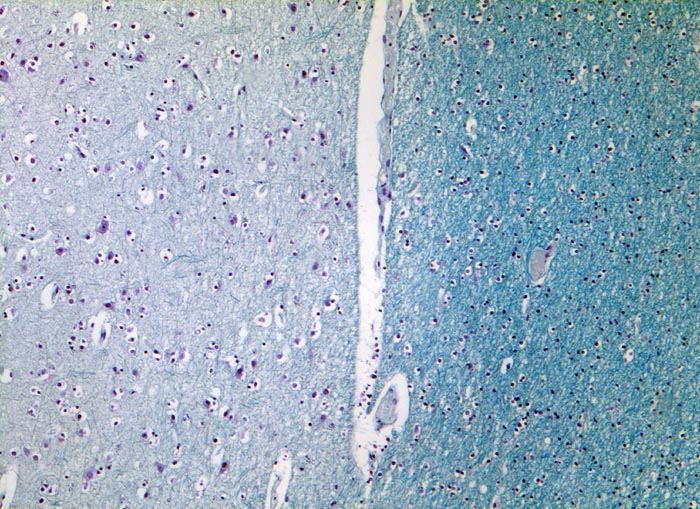

Grosshirnmark und Rinde

Normalbefund

Hirn temporal

Links im Bild die in der Markscheidenfärbung helle Hirnrinde mit grösseren Neuronen und Oligodendrozyten umgeben von einem Halo. Rechts das in der Markscheidenfärbung dunkel erscheinende Mark mit dichter liegenden Oligodendrozyten. In der weissen Substanz fehlen die Neurone.

Multiple periventrikulär gelagerte Entmarkungsherde im MRI

50

48